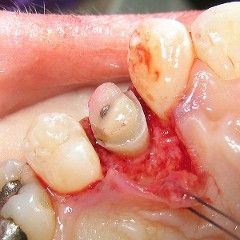

Crown lengthening surgery involves making an incision about the teeth. Then the gum tissue is carefully reflected back to fully expose the bone about the tooth. Bone is then removed from around the tooth--1 to 3 millimeters--depending on the individual case. Once the bone is smooth and shaped well, the gum tissue is returned to its position and sutured in such a fashion so that when it grows back into the tooth (just above the bone) it grows in lower on the root surface, below where the decay was.

Once the gums have healed fully, the dentist may then remove all the decay and safely restore the tooth. The restorative material (crown or filling) may now be kept well away from the gum attachment. Dental care professionals speak of a "biological width." This is the distance that a restoration must stay away from the gum attachment. It is about 1.5 to 2.0 millimeters. Allowing a restorative material any closer to the attachment can produce significant inflammation in the tissue. When the restorative material is directly into the attachment, severe inflammation occurs as the attachment is breached and it must be avoided.